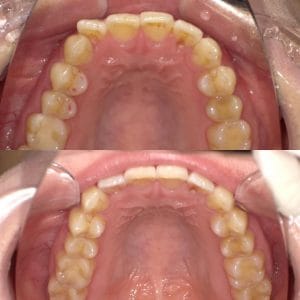

ワイヤー矯正

Case006 – ワイヤー矯正

片顎抜歯を行い、主に上の前歯の歯並びを矯正した症例です。

Case005 – ワイヤー矯正

Case004 – ワイヤー矯正

上下左右4本の抜歯を行い、全体の歯並びを矯正した症例です。

Case003 – ワイヤー矯正

Case002 – ワイヤー矯正

下の歯が前に出てしまう、いわゆる「受け口」を矯正した症例です。

Case001 – ワイヤー矯正